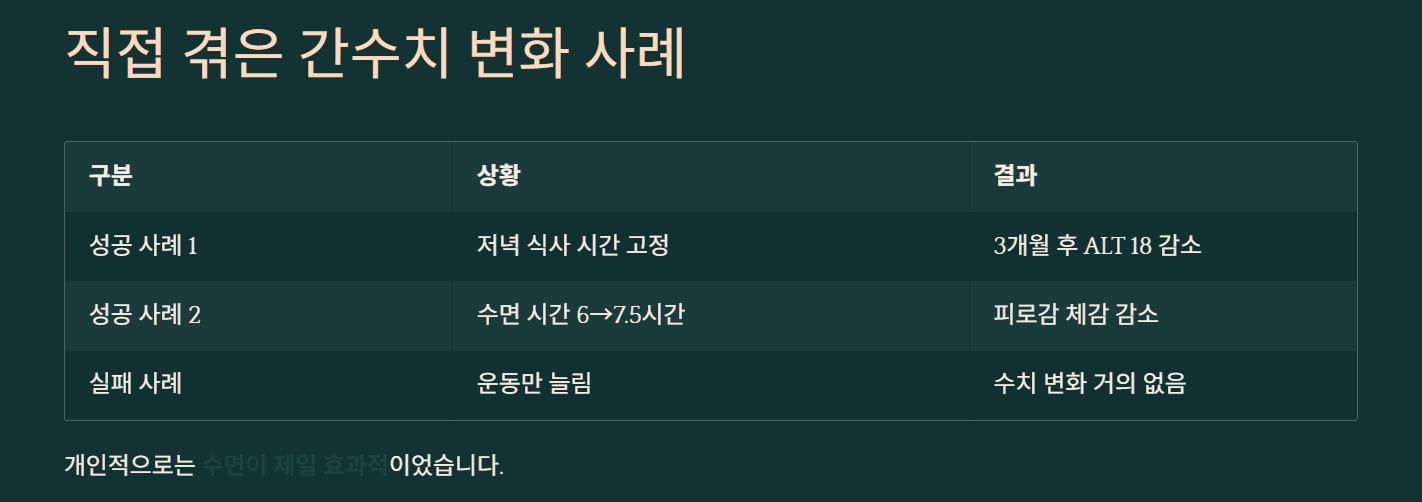

제가 겪은 간수치 변화 3가지 확인하기

| 구분 | 상황 | 결과 |

| 성공 사례 1 | 저녁 식사 시간 고정 | 3개월 후 ALT 18 감소 |

| 성공 사례 2 | 수면 시간 6→7.5시간 | 피로감 체감 감소 |

| 실패 사례 | 운동만 늘림 | 수치 변화 거의 없음 |

개인적으로는 수면이 제일 컸어요. 생각보다 괜찮았어요.